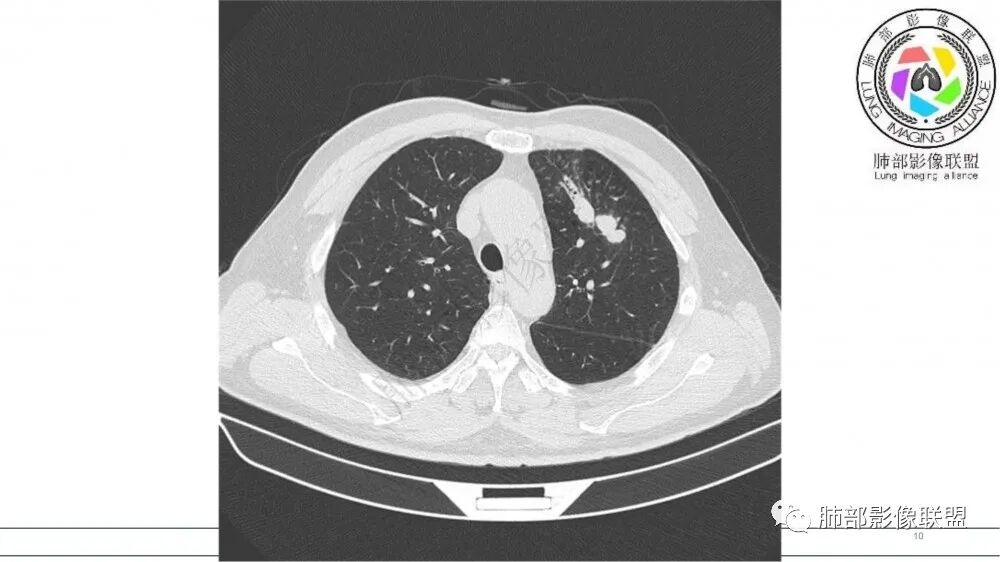

左肺上叶前段支气管内铸形生长软组织影,增强后均匀强化,远侧见斑片状磨玻璃影。考虑恶性病变,粘表?粘液腺?

老年男性,左肺上叶前段支气管内铸形阴影,增强后病灶不均匀强化,内部有坏死?远端可见斑片状阴影(阻塞性肺炎)。考虑恶性病变,老年人,鳞?类癌?粘表不能排除。

男,70岁,吸烟史,咳嗽,胸闷憋气一个月,左肺上叶不规则形软组织密度影,病灶沿支气管走形,周围见粟粒及棉絮样稍高密度影,增强扫描病灶内见少许坏死,考虑鳞癌可能,鉴别结核。

老年男性,肺气肿,吸烟史,左肺上支气管腔内铸型高密度影,呈指套状,远端多发树芽,增强不均匀强化,考虑鳞癌,鉴别小细胞癌

B3指套征,常规不是鳞癌就是ABPA,有强化丶血管造影征,倾向于鳞癌

老年男性,长期吸烟史。左上肺前段沿支气管走形的指套样病变,增强可见病灶强化(排除结核、ABPA(也无气喘症状)),远端多发点状高密度影。考虑恶性肿瘤,鳞癌可能性大。

指套征,扩张支气管内软组织强化,远侧肺野阻塞性炎,纵隔、左肺门肿大淋巴结;老年男性,吸烟,考虑鳞癌,鉴别小

指套征:是影像征象,胸部平片表现为手指状密度增高影,以肺门为中心呈放射状分布,CT显示扩张支气管内低密度黏液栓形成或实性病变,呈管状、树枝状或卵圆形密度增高影;支气管扩张伴近端梗阻时,扩张支气管内部黏液分泌物不能排出而形成。可以伴随远端空气潴留征、阻塞性炎症。